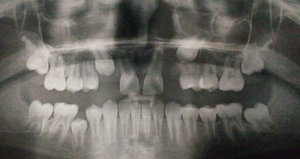

Мне 28 лет. Мне удалили молочный зуб в подростковом возрасте, а настоящий не вырос. В результате остальные зубы внизу постеренно сдвинулись и заполнили частитно пустое пространство. Стоматолог предложил поставить брекеты, чтобы сдвинуть зубы на их прежнее место, а затем поставить имплант.

Имеет ли это смысл и что будет, если оставить все как есть?

Конечно имеет смысл, ваш стоматолог прав, а смысл в том, что будет полный зубной ряд и симметрия. В противном случае, понемногу, весь зубной ряд будет смещаться в сторону дефекта.